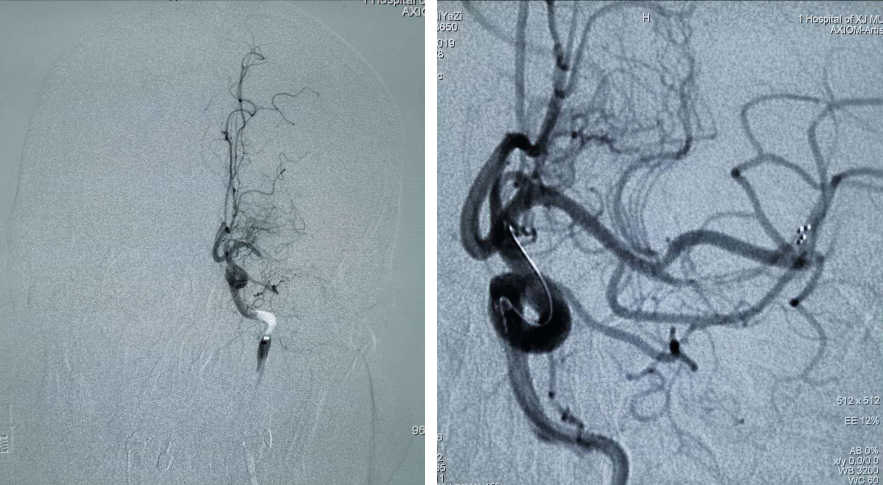

全脑血管造影术提示:左侧颈内动脉起始部闭塞,左侧颈内颅内段未见显影;在颈内动脉起始部采用Rebar-18微导管采用SWIM(支架取栓+抽吸)技术。

支架于血栓充分贴合后取栓系统回收,复查造影示:左侧大脑中动脉远端未见显影;Silverspeed14微导丝携带Rebar-18微导管到达左侧颈内动脉M2段,采用SWIM技术后复查造影血流通畅。

PT导丝携带颈动脉支架通过左侧颈内动脉狭窄处,释放支架后复查造影支架贴壁良好狭窄率不足10%。

术后复查左侧颈内动脉颅内段血供良好